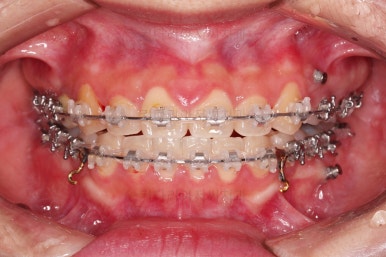

부산치아교정 이번 치료의 핵심인데요.

결손 부위에 미니스크류를 이용해서 뒤쪽 어금니들을 결손 부위로 앞으로 앞으로 계속 당겨줍니다.

얼굴모습에서의 중앙선도 지속저으로 체크하면서 한 쪽으로 치우침 없이 마무리를 해야 하고요.

틈새가 줄어들 때 까지 같은 작업을 반복합니다.

점점 틈새가 붙어가는게 보이죠?

계속 반복합니다.

틈새는 거의 다 붙어가는데 교합이나 중앙선 등을 위해 추가적으로 밀고 당기기를 해줍니다.

디테일을 좀 더 맞추고 부산치아교정 마무리를 합니다.

치아 갯수 및 사이즈 문제로 위아래의 정중선은 100% 일치시키긴 힘들지만 가능한 선에서 최대한 맞추었고요.

윗니가 1개 없는 상태에서의 교합도 잘 맞추고 마무리를 했습니다.